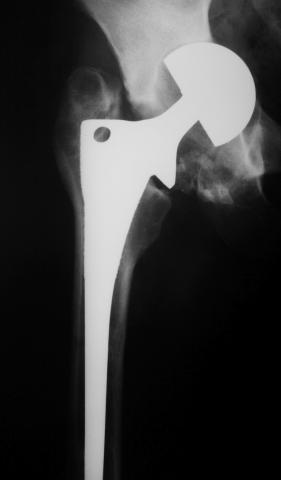

Лечился в стержневом аппарате по месту жительства. АВФ демонтировали через полгода из-за воспаления в области стержней (рис 2). После демонтажа в течение месяца больной лихорадил до 38*, были боли в бедре. Эти явления исчезли после курса антибиотиков. Через год после травмы в ЦРБ ему имплантировали биполярный протез (рис 3). Рана зажила первично. Ходил с костылями, слегка приступая на ногу. На контрольных осмотрах выявлена прогрессирующая протрузия (рис 4-6).

Сегодня выполнили открытую биопсию параартикулярных тканей. После капсулотомии выделилось около 5 мл гноя. :( Образцы, конечно же, направили в баклабораторию, однако это скорее формальность...

Следующий этап лечения - Girdlestone...